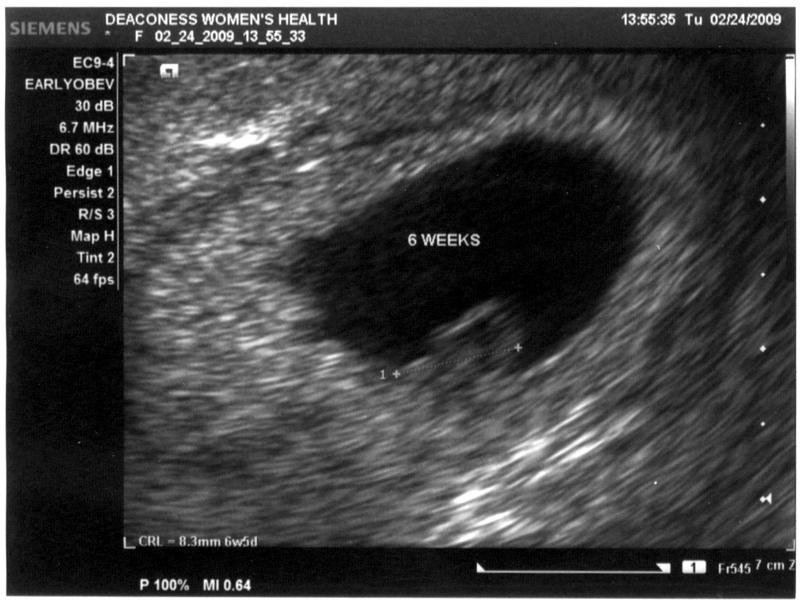

Anyway.  Fast forward 8 weeks.  I'm 12.5 weeks along now,  and still full of worry and paranoia.  I thought after a couple of doctor's appointment, seeing the heart beat of the baby, I would calm down.  But no such luck.  I still wake up in the morning, wondering if the baby is safe and sound.  This is why some women get dopplers I guess.  It's a little better than earlier weeks, but at week 12, I still worry.  My next appointment isn't until the 23rd of April, so I'm getting really antsy.  Kris calls it "ultrasound withdrawl".  I had some spotting earlier (weeks 6 and 8), which really got us worried, and because of the spotting, we got a couple of early ultrasounds in.  Now that I won't get one for four more weeks, I'm just going crazy!

6 week ultrasound

Ultrasound at 6 weeks